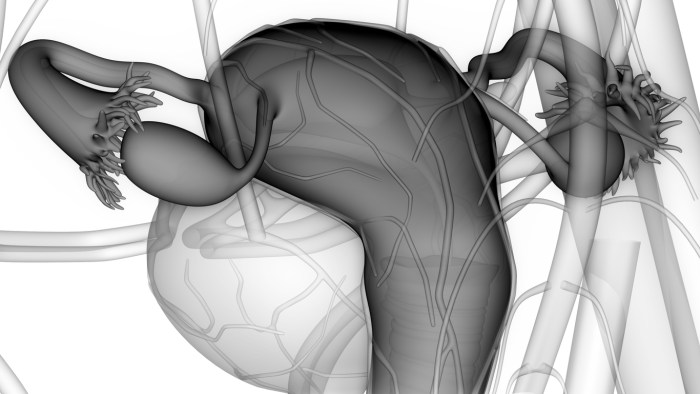

Anatomy of the reproduction organs in a woman

Anatomy of the female reproductive system Gynecology